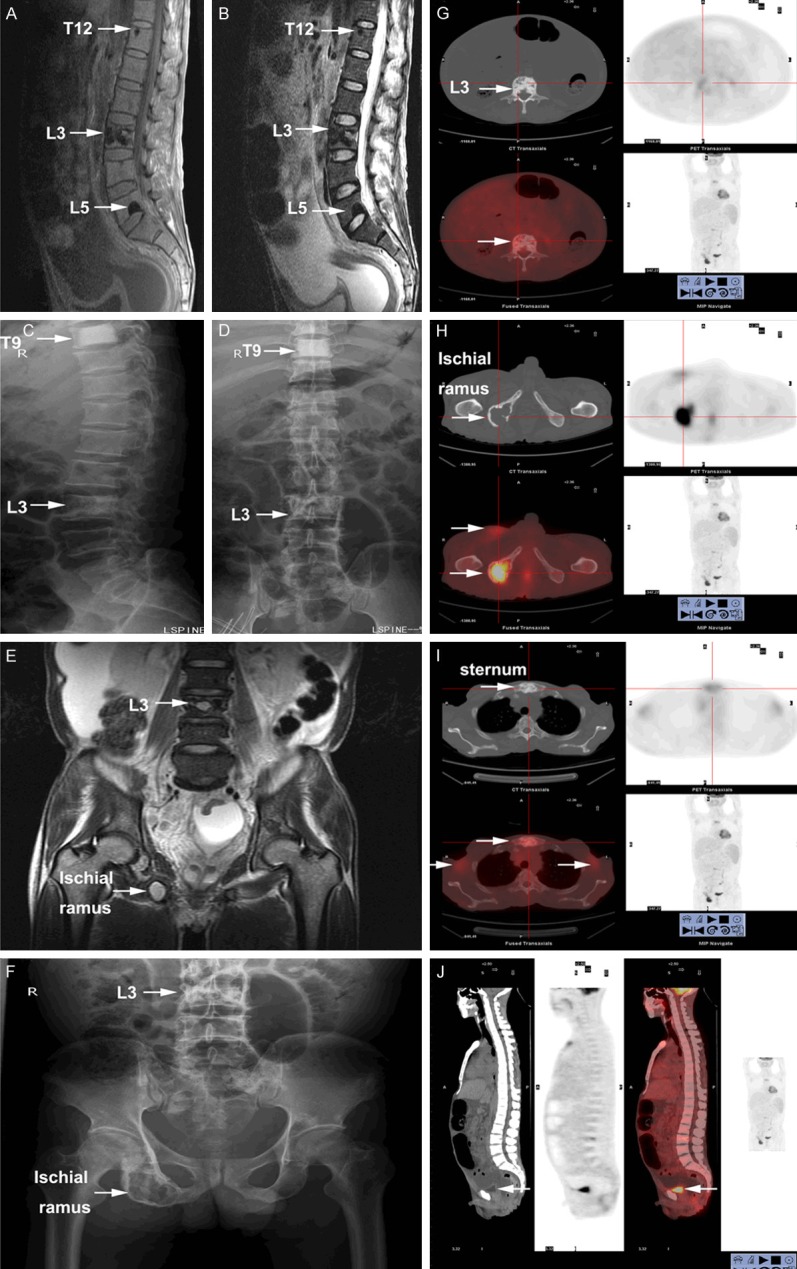

- Can be sclerotic, lytic with sclerotic rim, or mixed ("soap bubble" appearance)

- Most common in axial skeleton — pelvis, spine, ribs, proximal extremities

- Most are less than 1 cm — CT with bone windows far more sensitive than plain X-ray

- ~50% have a single lesion; ~50% have multiple

- CT (chest/abdomen/pelvis) with bone windows — NOT plain X-ray

- PET/CT if available

Clinical imaging: Shi XF et al., "Multimodal imaging and clinical characteristics of bone lesions in POEMS syndrome," Int J Clin Exp Med 2015;8(5):7467-76, PMC4509235. Chen YH et al., CCR3, PMC4831386. Case Reports in Medicine, PMC3195534. All images reproduced under Creative Commons licenses.